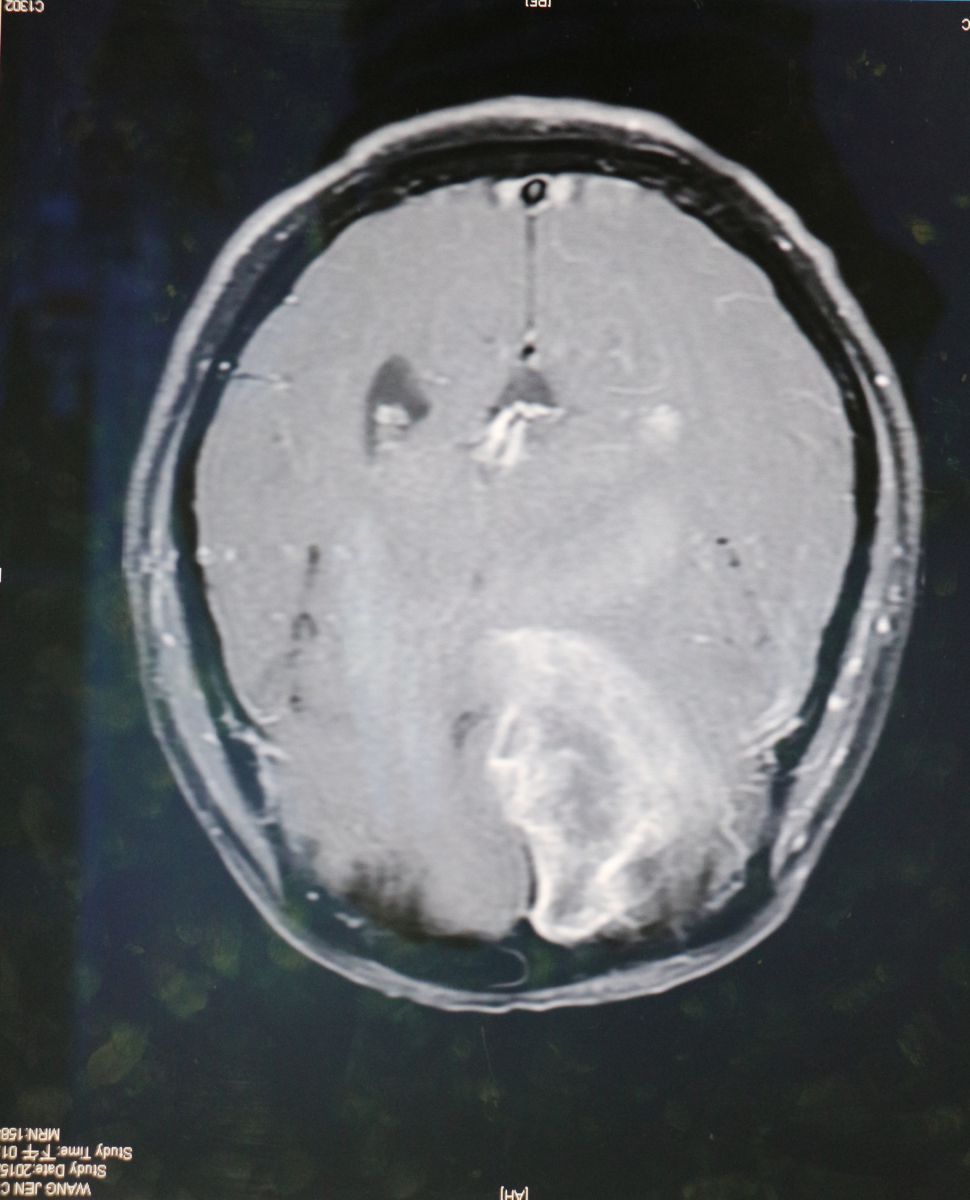

臺北市立聯合醫院和平婦幼院區牙科主治醫師趙書群說,臨床上,牙痛雖然也會引發頭部不適的感覺,但像患者所述的疼痛感,以及各項口腔檢查皆無問題的情況下,判定應該不是牙齒問題,因此將患者轉診至神經外科,經核磁共振血管攝影,終於確診為動靜脈血管畸形(AVM)所引發的疼痛。